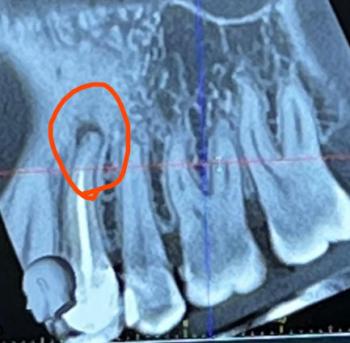

Dental Case Analysis: Lower Arch With Braces and Multiple Carious Lesions

The image shows the lower dental arch with fixed orthodontic brackets in place. Several posterior teeth exhibit dark cavitated areas, consistent with active dental caries. Oral hygiene challenges are evident around brackets and molars.

Multiple lower molars with visible dark cavities